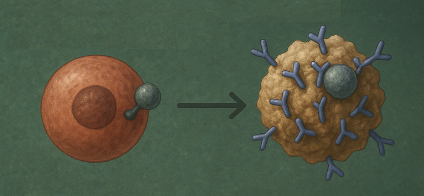

No corpo, os iões metálicos podem ligar-se firmemente às células, e proteínas do indivíduo, mascarando-as e tornando-as irreconhecíveis para o sistema imunitário*, levando a uma resposta de ataque autoimune, o que pode agravar situações autoimunes que a pessoa já tinha ou criar novas perturbações auto-imunitárias.

(*para precisão científica, tecnicamente diz-se: modificação de epítopos autólogos, ou seja, haptenização; Em indivíduos suscetíveis, as células T reconhecem falsamente as proteínas modificadas como estranhas e iniciam um ataque autoimune).